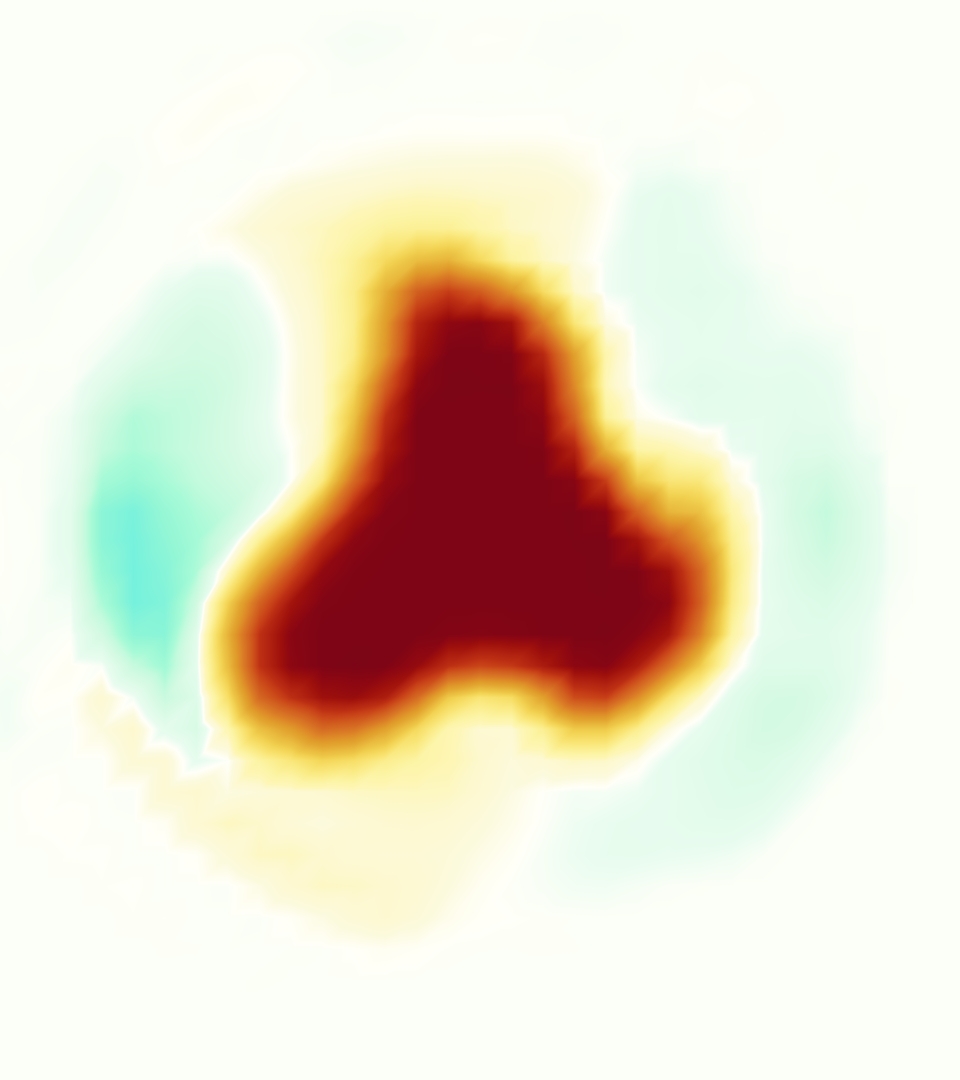

Slice views of the (axial) component of fluid velocity in the axial plane, orthogonal to the flow direction, show that the simulation replicated the development of the jet over the cardiac cycle. At each phase, the simulation matched the forward speed of the core of the jet and the locations of reverse flow back towards the valve annulus. While there are some differences in the shape of the jet at certain phases and locations, the simulation clearly produced the general dynamics of the cardiac cycle that are seen in the experiment.

At = 0, the axial slice directly at the valve annulus shown in columns 1 and 2 in Figure 6, there was excellent agreement between the simulation and experiment over the cardiac cycle in the speed and shape of the jet through the valve. In both cases, the axial velocity increased as the flow accelerated during systole and the valve leaflets opened, then decreased during diastole with slight negative velocity before the valve leaflets were fully closed. The forward flow through the valve annulus did not form a full circle, but rather developed a triangular shape with a point of the triangle forming along the interior curve of the vessel, at the bottom of the axial slices. At = 0, the points of this triangular jet shape aligned with the commissures of the valve. This shape persisted during peak systole and was well-matched by the simulation.

The axial slice = 0.625 cm, shown in columns 3 and 4 in Figure 6, cut through the support scaffolding of the valve and the leaflets when they are open. In the experimental data, the shape of the jet changed as it moved downstream. A triangular shape occurred, but the points were then aligned with the middle of each open leaflet as opposed to the commissures. Those points were also more rounded than they were at = 0. The peak velocity of the jet was faster at = 0.625 cm than at = 0, as the flow accelerated through the open valve leaflets. The simulation produced these features at = 0.625 cm. The triangular shape of the jet shifted similarly, and its speed increased compared to the upstream slice. As the flow decelerated into diastole, the jet shape remained roughly triangular but diminished in intensity before disappearing after valve closure.

The jet continued to develop at = 1.25 cm, an axial slice immediately downstream of the valve scaffolding and open leaflets, shown in columns 5 and 6 in Figure 6. In the experimental data, the points of the triangular jet shape extended further towards the vessel wall. In addition, regions of reversed flow developed in the locations downstream of the commissures, resulting in curved sides to the shape of the jet. Each tip of the jet was unique, due to variations in the individual leaflets in the physical bioprosthetic valve. These variations are apparent in the velocity fields, possibly because the jet edges are similar enough cycle to cycle that irregularities are still being captured even with phase averaging. Further discussion of these features can be found in Schiavone et al. [39], which showed that the jet tip shapes occurred in different pulmonary anatomies, demonstrating that they were likely due to inherent properties of each leaflet. The leaflets in the mathematical model of the valve are identical, so these nuances in leaflet variation could not be replicated. The simulation did capture some of the extension of the tips of the jet, as they were closer to vessel wall at slice = 1.25 cm than = 0.625 cm. The curves in the triangular sides of the jet were also present in the simulation, though they were less pronounced than the experimental data. At both = 0.625 cm and = 1.25 cm, the jet shape in the simulation was smoother than the jet in experiment. It is possible that the free edges of the leaflets in the mathematical model are not fully replicating the behavior of the physical leaflets of the bioprosthetic valve, in particular the amplitude or frequency of leaflet flutter, leading to the variations seen in the jet shape at = 1.25 cm downstream of the leaflet edges. The simulation, however, does capture the key features of the triangular shape and speed of the jet. Overall, qualitative comparisons demonstrated that the simulation reproduced key features of the flow during systole and diastole.